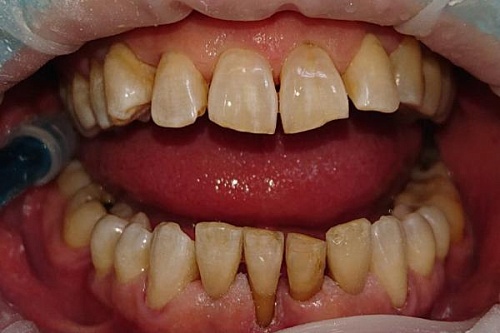

Профессиональная гигиена ультразвуком и Air Flow

Лечение зубов с использованием профессиональной гигиены, ультразвука и технологии Air Flow, мужчина 32 лет.

Профессиональная гигиена ультразвуком и Air Flow До

Профессиональная гигиена ультразвуком и Air Flow После